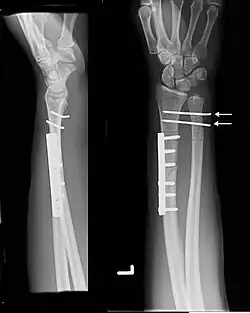

Galeazzi fracture

| Galeazzi fracture. Arrow points at the dislocated ulnar head | |

The Galeazzi fracture is a fracture of the distal third of the radius with dislocation of the distal radioulnar joint. It classically involves an isolated fracture of the junction of the distal third and middle third of the radius with associated subluxation or dislocation of the distal radio-ulnar joint; the injury disrupts the forearm axis joint.[1]